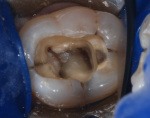

Here’s Why You Should Just Get That Crown Your Dentist Recommended

The patient said, “Don’t say I told you so.”  I said, “I don’t have to, you just did.” She said, “This is going to cost twice as much now, isn’t it?”  I said, "Yes.” “Will the root canal make the pain go away?”  “Yes.” “Well then, let’s get this over with.”  “Open, please.” It didn’t have to be this way. ... read more »